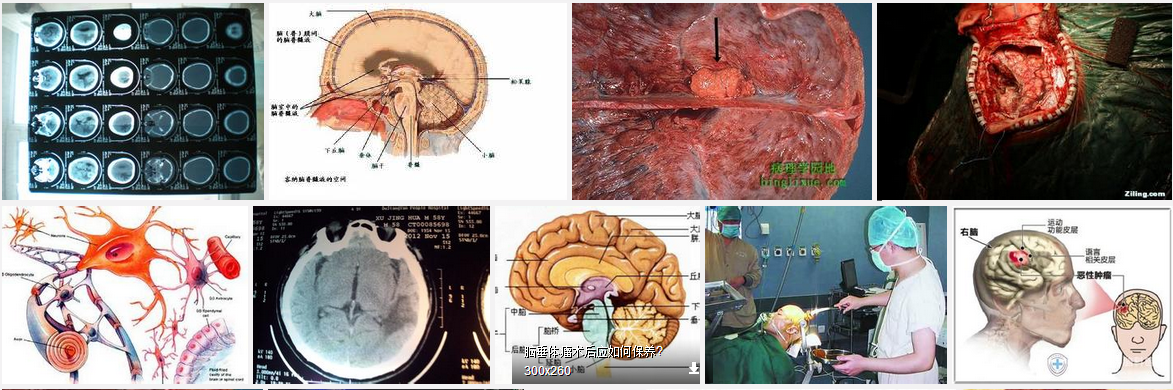

2.CT扫描:在脑膜瘤的诊断上,CT扫描已取代同位素脑扫描、气脑和脑室造影、脑膜瘤多为实质性且富于血运,最适合于CT检查,其准确性能够达到发现1cm大小的脑膜瘤。在CT扫描图像上,脑膜瘤有其特殊征象,在颅内显示出局限性圆形密度均匀一致的造影剂增强影像,可并有骨质增生,肿瘤周边出现密度减低的脑水肿带,相应的脑移位,以及脑脊液循环梗阻引起的脑积水征象。

2.CT扫描 CT对视神经肿瘤的诊断尤其是肿瘤内的钙化显示非常有价值。 CT识别病变的性质主要根据视神经增粗的形状和密度。所以判断眶内肿块是否为视神经本身的增粗是鉴别视神经肿瘤和球后其他肿瘤的关键。由于CT的容积效应或视神经与肿瘤密度值接近时,横轴位CT有时无法区别是视神经本身的增粗还是视神经一侧的肿瘤。此时冠状CT或MRI可能是较好的鉴别方法。

薄层CT扫描可较好地显示视神经鞘脑膜瘤。由于肿瘤无明显包膜,在横轴位或冠状CT显示肿瘤边界欠清,呈浸润性增长。CT诊断视神经鞘脑膜瘤主要根据病变的形状和位置。肿瘤可呈管状、块状、梭形、不规则形和偏心形。除此之外,增强CT显示的“车轨征”(增强的管状高密度肿瘤与不增强的视神经之间的密度差异,但如果眶尖部肿瘤呈块状也可显示低密度的线状视神经被高密度的肿瘤包绕)和肿瘤内钙化是视神经鞘脑膜瘤较典型的CT征。“车轨征”也见于其他视神经鞘的病变如视神经周围炎性假瘤、视神经周围炎等视神经鞘的病变。视神经呈明显的管状增粗时诊断容易,而仅表现为眶尖肿块时在CT上不易和其他眶尖肿块鉴别。

CT可提供良好的眶骨和鞍旁解剖结构,可显示肿瘤内钙化和脑膜瘤合并的骨增生。颅内和眶内脑膜瘤增强CT均显示肿瘤有增强现象。中度大小的脑膜瘤颅内蔓延,增强CT也可显示,但扁平型或体积较小的肿瘤向颅内蔓延,尤其是直径<5mm的肿瘤可能需要MRI成像,CT的作用有限。CT虽可显示肿瘤引起的局部骨增生(视神经鞘脑膜瘤较少见)、肿瘤内钙化,但对视神经管内和(或)颅内肿瘤的显示较差。CT缺点为离子辐射,不能直接多角度显像,部分容积效应和骨伪影等影响了颅内和视神经管内脑膜瘤的显示。

3.MRI 由于有较好的软组织显示,所以在发现和估计视神经鞘肿瘤上非常重要。眶内脑膜瘤类似颅内脑膜瘤有较特征性的MRI信号。多数肿瘤在TlWI与脑皮质比较呈等或低信号,易于鉴别。T2WI上肿瘤信号与组织病理发现有关,多数为中信号,如肿瘤内有钙化是以低信号为特征的。较小的脑膜瘤在非增强MRI可能不被发现。

Gd-DTPA增强后可显示肿瘤中、高度增强,增强MRI+脂肪抑制是显示脑膜瘤尤其是颅内或视神经管内肿瘤蔓延最好的方法,对于其他视神经病变也一样。体积较小或扁平的脑膜瘤颅内蔓延时只有靠增强MRI+脂肪抑制显像才能显示。Lindblom报告增强MRI检查13例视神经鞘脑膜瘤,其中11例发现颅内蔓延。增强MRI扫描中横轴位和冠状位显示较好,矢状位常因扫描角度关系显示欠佳。